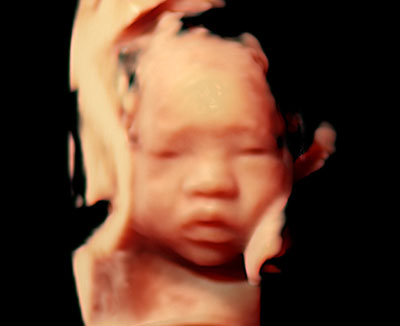

超音波検査(4Dエコー)

当院では最新の4Dエコーを導入しています。4Dエコーでは、胎児の立体的な画像をリアルタイムで動画として見ることができ、胎内の赤ちゃんの動き(あくびや指しゃぶりなど)を鮮明に表現できます。

最新の機種では基本画質の向上により、心臓や血管の血液の流れをより繊細に、装置のディスプレイ上で確認できる「カラードプラ」の感度が向上しました。